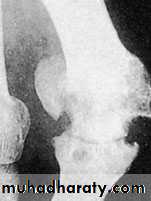

To start with the deformity is mild, with time it get more severe, immobile and cannot be corrected manually, later osteoarthritis occurs with stiff and painful first metatarsophalangial joint.The lst. metatarsal head looks thick and widened, and because of rubbing with shoe wear on its medial side there will be the formation of thick bony exostosis and over it there is a protective synovial bursa (the bunion) that may get swollen, inflamed or infected.

X-ray:

Taken with the patient standing to show the degree of metatarsal and hallux angulations.Also it shows the state of the joint being normal, arthritic or subluxated.